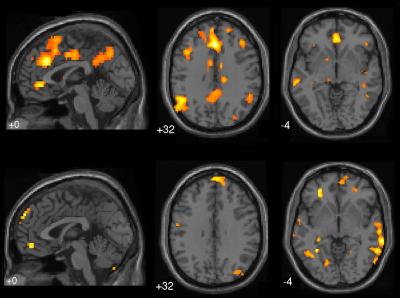

The study, published in the Proceedings of the National Academy of Sciences , finds that activity in numerous brain regions increases when our minds wander. It also finds that brain areas associated with complex problem-solving – previously thought to go dormant when we daydream – are in fact highly active during these episodes.

For the study, subjects were placed inside an fMRI scanner, where they performed the simple routine task of pushing a button when numbers appear on a screen. The researchers tracked subjects' attentiveness moment-to-moment through brain scans, subjective reports from subjects and by tracking their performance on the task.

Until now, the brain's "default network" – which is linked to easy, routine mental activity and includes the medial prefrontal cortex (PFC), the posterior cingulate cortex and the temporoparietal junction – was the only part of the brain thought to be active when our minds wander.

However, the study finds that the brain's "executive network" – associated with high-level, complex problem-solving and including the lateral PFC and the dorsal anterior cingulate cortex – also becomes activated when we daydream.

"This is a surprising finding, that these two brain networks are activated in parallel," says Christoff. "Until now, scientists have thought they operated on an either-or basis – when one was activated, the other was thought to be dormant." The less subjects were aware that their mind was wandering, the more both networks were activated.